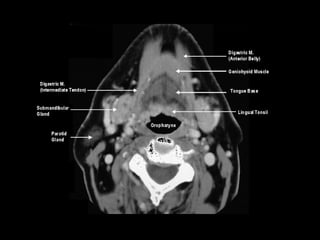

Radiographers use medical imaging equipment like X-rays and MRIs to produce images of patients' internal structures and organs. They are responsible for positioning patients, operating scanning machines, and ensuring quality images. Radiographers must have strong attention to detail, excellent communication skills, and the ability to work well under pressure to accurately capture anatomical features and diagnose any abnormalities.